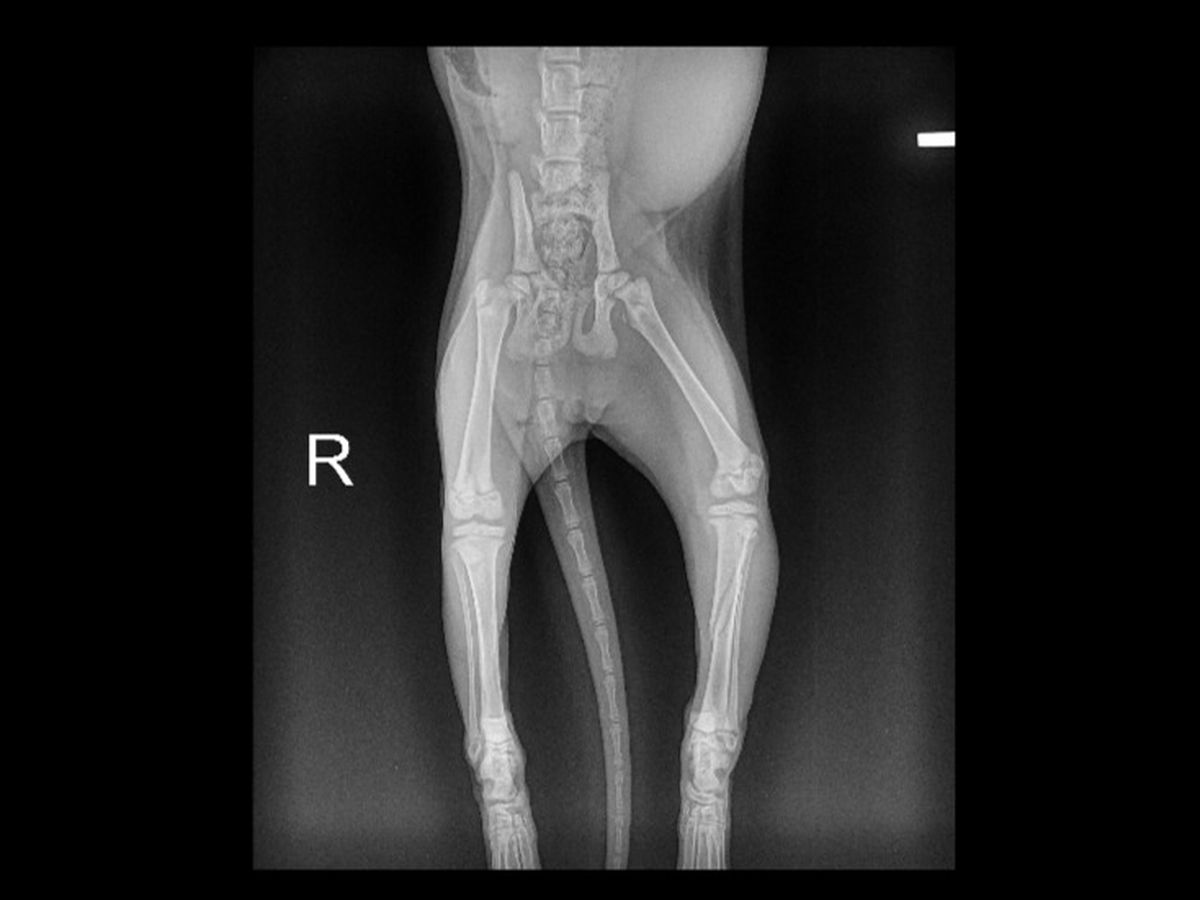

Hi, my name is Diamond and I am a shining little gem. I was born in a heated shed with my mama and siblings. It was not very nice and the old man who had been feeding my mom for a long time wanted desperately to find a good place for us to grow up. He drove two hours to get to Pet Patrol to make sure we would be OK. I am known as a real go-getter and an active little girl and when I was finally adopted into a family, I didn’t slow down one bit. Only a few weeks in my new owner called Pet Patrol very upset and very concerned about me. Understandably. I had broken my leg. Not being used to a house and being a kitten and kind of dumb, I jumped off of something super-duper high and fractured my back leg. My owner wasn’t coping well and didn’t know what to do with me, so I was relinquished back to Pet Patrol right after he dropped me off at the vet. So here I am. Waiting to know if I need surgery or can my bones be set and cast. The cost is high. The time for healing is very involved, and I will not be able to come out of a big cage for at least 4 to 5 weeks. But I’m willing to do it because I know I will get a lot of attention and will get better. Would you be able to help me to be able to have whatever vet care is needed, and to take the burden off Pet Patrol financially. I am a good girl, I just don’t have much depth perception, I guess.